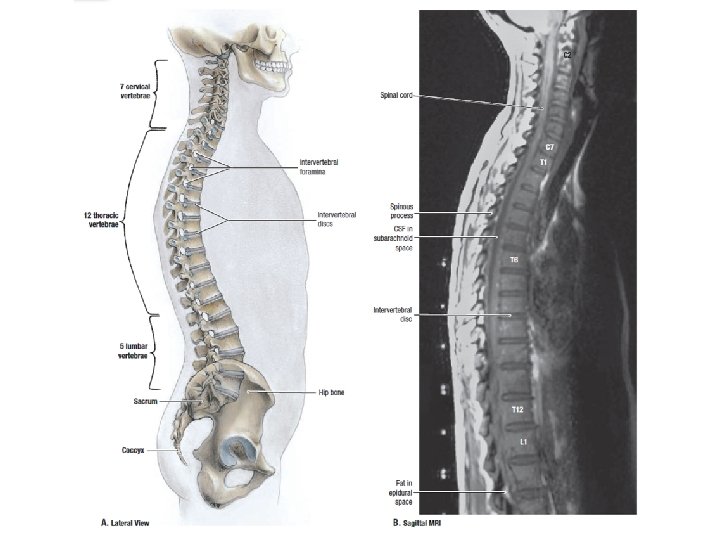

„Gerincesek törzse” Gerincoszlop - Mozgásban betöltött szerep - Gerincvelő védelme - ált 33 -35 csigolyából áll: - 7 nyaki (v. cervicales) - 12 háti (v. thoracicae) - 5 ágyéki (v. lumbales) - 5 keresztcsonti (sacrum) - 4 -6 farokcsonti (v. coccygeae) (coccyx)

Cervicalis lordosis Thoracalis kyphosis A gerinc egészben A gerinc görbületei születéskor még nincsenek jelen, a mozgás fejlődésével párhuzamosan alakulnak ki. A szerepük a rugalmasabb erőátvitel biztosítása, energiát nyelnek el (rugó!) Oldalirányú elhajlás (scoliosis) normálisan minimális. Lumbalis lordosis Sacralis kyphosis

Gerincvelő, gerincvelői idegek 8 cervicalis C 1 -8 – megfelelő csigolya felett 12 thoracalis Th 1 -Co 1 – megfelelő csigolya alatt 5 lumbalis A lumbalis illetve sacralis gyökök több csigolyányit haladnak lefelé a durazsákon belül: 5 sacralis 1 coccygealis 31 pár cauda equina lumbalis cisterna